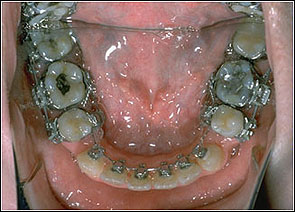

STEP 2. Partial canine retraction

Stainless Steel 016,016*022